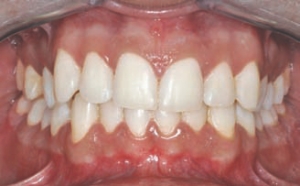

Aesthetic Rehabilitation Of Maxillary Central Incisors Using All Ceramic Crowns (Procera™) — A Case Report Involving Long Term Provisionalization

Maxillary anterior crowns provide an exciting challenge to our artistic and technical abilities and call upon our knowledgeof smile design principles of proportion, symmetry, harmony and tooth morphology. Smile rejuvenation can positively impact a patient’s selfesteem and emotional health through improved appearance. 9 Excellent soft tissue health and correct tooth contours and emergence profiles are … Read more